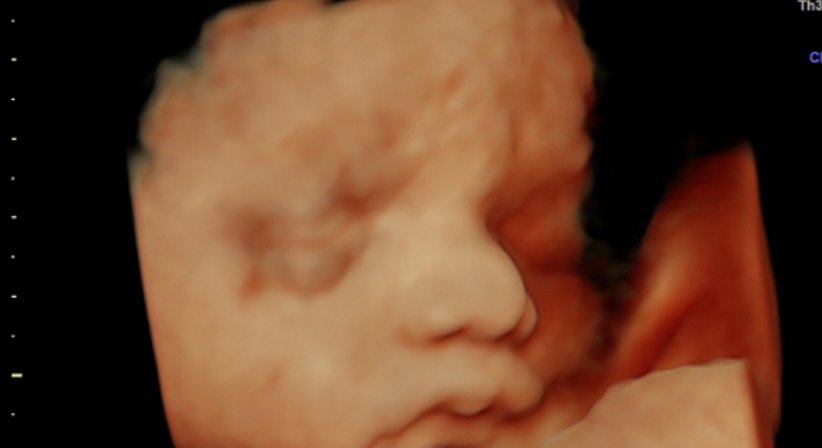

3D/4D Ultraschall

Bei meinen Patientinnen wird bei guter Kindslage auf Wunsch auch ein 3D Bild angefertigt.